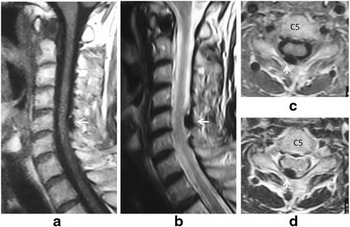

Acute neck pain caused by pseudogout attack of calcified cervical yellow ligament, a-d)MRI image